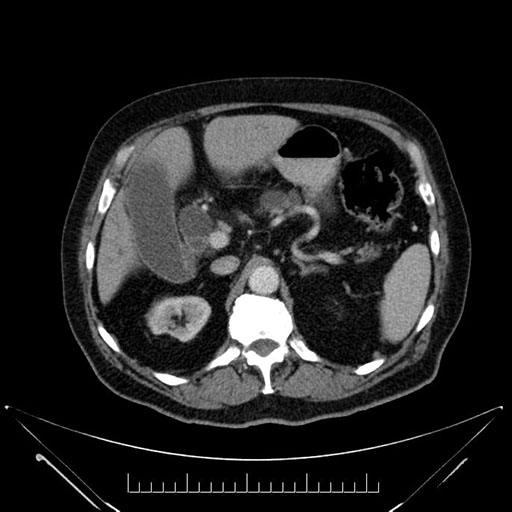

Axial - stented